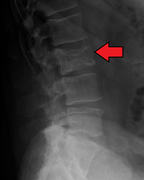

Bone pain affects almost 70% of people with multiple myeloma and is one of the most common symptoms.[2]:653[22] Myeloma bone pain usually involves the spine and ribs, and worsens with activity. Persistent, localized pain may indicate a pathological bone fracture. Involvement of the vertebrae may lead to spinal cord compression or kyphosis. Myeloma bone disease is due to the overexpression of receptor activator for nuclear factor κ B ligand (RANKL) by bone marrow stroma. RANKL activates osteoclasts, which resorb bone. The resultant bone lesions are lytic (cause breakdown) in nature, and are best seen in plain radiographs, which may show "punched-out" resorptive lesions (including the "raindrop" appearance of the skull on radiography). The breakdown of bone also leads to the release of calcium ions into the blood, leading to hypercalcemia and its associated symptoms.[23]

The diagnostic examination of a person with suspected multiple myeloma typically includes a skeletal survey. This is a series of X-rays of the skull, axial skeleton, and proximal long bones. Myeloma activity sometimes appears as "lytic lesions" (with local disappearance of normal bone due to resorption) or as "punched-out lesions" on the skull X-ray ("raindrop skull"). Lesions may also be sclerotic, which is seen as radiodense.[70] Overall, the radiodensity of myeloma is between −30 and 120 Hounsfield units (HU).[71] Magnetic resonance imaging is more sensitive than simple X-rays in the detection of lytic lesions, and may supersede a skeletal survey, especially when vertebral disease is suspected. Occasionally, a CT scan is performed to measure the size of soft-tissue plasmacytomas. Nuclear Medicine Bone scans are typically not of any additional value in the workup of people with myeloma (no new bone formation; lytic lesions not well visualized on nuclear bone scan).

Pathological fracture of the lumbar spine due to multiple myeloma